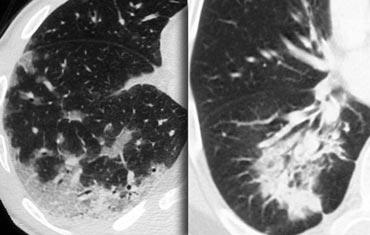

Ví dụ minh họa

Hình ảnh bên trái mô tả bệnh nhân có các nốt phân bố ngẫu nhiên do lao kê.

Phân bố ngẫu nhiên là kết quả của sự lan tràn theo đường máu của nhiễm trùng.

Hình ảnh được trình bày minh họa dạng nốt ngẫu nhiên điển hình ở bệnh nhân mắc bệnh mô bào Langerhans (LCH).

LCH là một bệnh hiếm gặp được đặc trưng bởi nhiều nang không đều, chủ yếu ở bệnh nhân có tiền sử lạm dụng nicotine.

Trong giai đoạn sớm, LCH biểu hiện như một bệnh dạng nốt (hình).

Theo thời gian, các nốt này tạo hang và tiến triển thành nang.

Cũng như các bệnh liên quan đến hút thuốc khác, có sự ưu thế ở thùy trên.